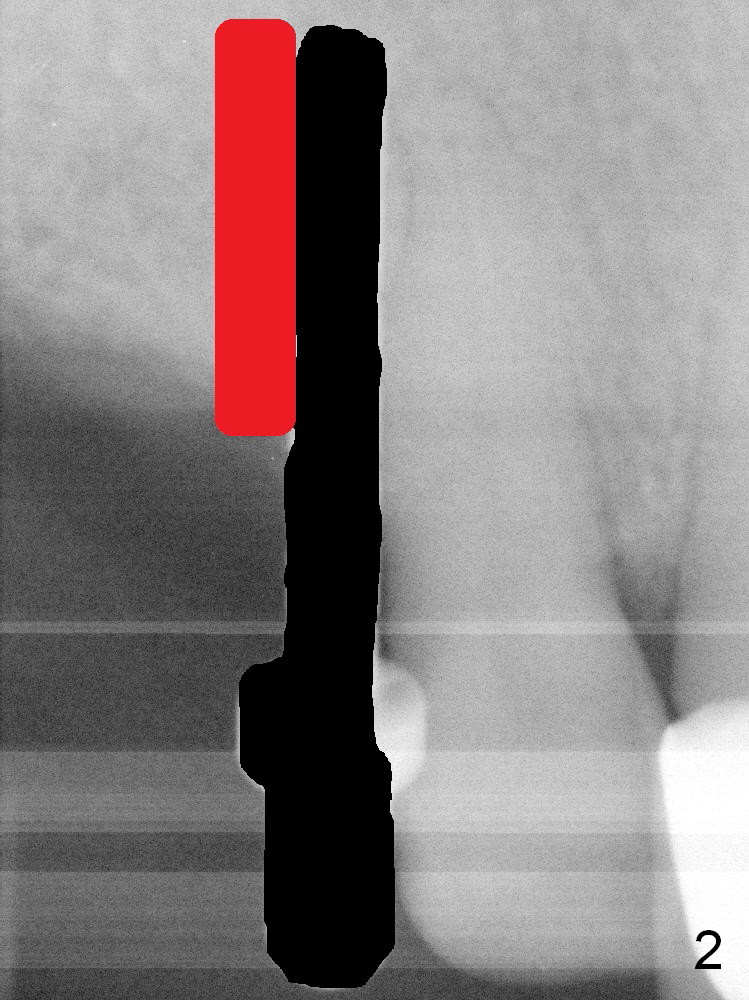

After initial osteotomy at the site of #6 with a 2 mm pilot drill at 11 mm, a parallel pin is inserted (Fig.1). It appears close to the neighboring root (dashed line), although it does not look so close clinically. When the parallel pin is removed (Fig.2 black area), the osteotomy is moved distally (red area) with a Lindamann bur. Then the osteotomy is deepened and enlarged (Fig.3 green area). When a 4x17 mm tissue-level implant is placed (Fig.4 I), a ball abutment (A) is inserted without enough clearance. The clearance with a ball abutment at the site of #3 is also not sufficient. It appears that crowns have to be fabricated prior to fabrication of the upper removable partial denture.